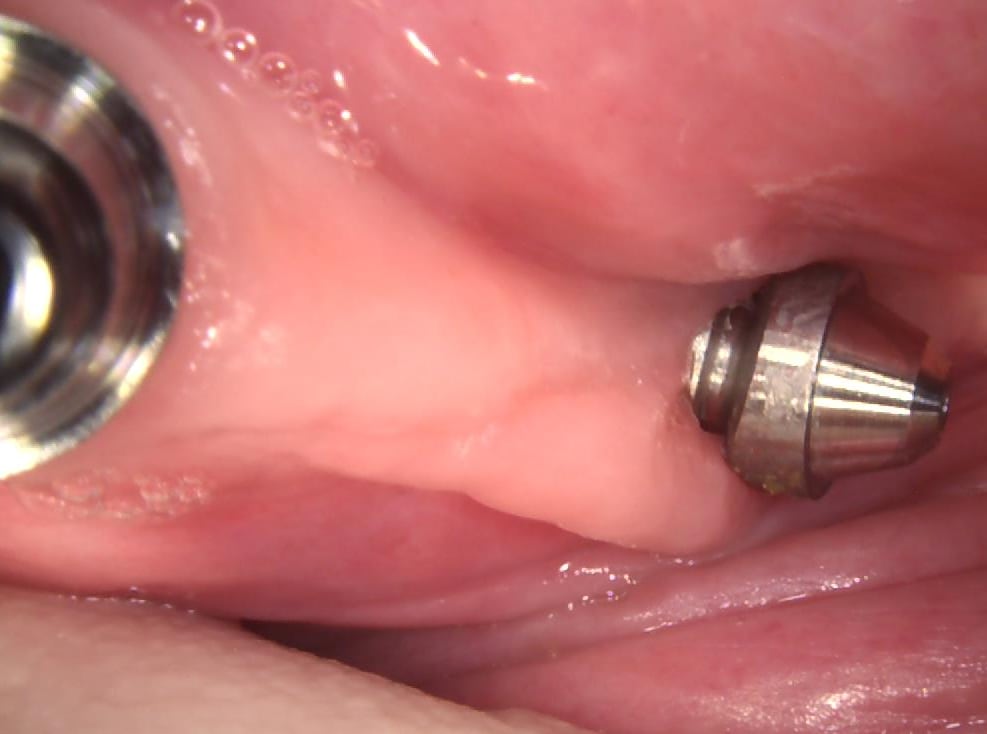

et en position de 35&1/2 implant terminal , il y a un multi unit étrange qui compense l axe .

ce que je ne comprends pas , ç est l utilité de cet espace libre réceptacle de saloperies entre ce multi unit et l implant .

dejà le 1 er jour de la pose du prov par l implanto elle se plaignait d avoir une " bobine de fil " sous l appareil prov à cet endroit .

ce que ce que je ne saisis pas , ç est que cette piece est prevue lorsque l implant est tordu /à la crete .

mais alors pourquoi elle est biseauté en mesial ?? en distal j aurais déjà plus compris . là ça augmente l espace .

et en plus elle déborde de ce même coté